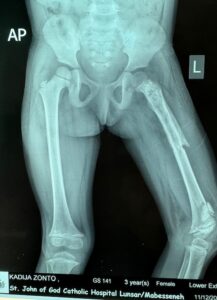

Das operative Team behandelt beispielsweise veraltete Knochenbrüche oder infizierte Gliedmassen nach offenen Knochenbrüchen oder durch Weichteilverletzungen, während sich Frau Sixt um die Ausstattung, den Betrieb und die Ausbildung in dem von GloboLab am Krankenhaus schon vor vielen Jahren

eingerichteten, leider immer wieder von Unterbrechungen und personellen Veränderungen zurück geworfenen Labor bemüht. Hauptziel dieses Labors war von Beginn an die genaue Identifizierung von Keimen in der Klinik St. John of God sowie die Testung der Empfindlichkeit bzw. Resistenz gegenüber den verfügbaren Antibiotika.